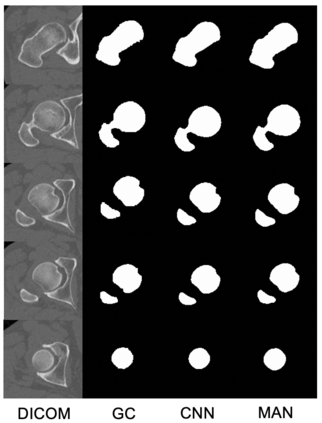

Osteoporosis is a common bone disease that increases the risk of bone fracture. Hip-fracture risk screening methods based on finite element analysis depend on segmented computed tomography (CT) images; however, current femur segmentation methods require manual delineations of large data sets. Here we propose a deep neural network for fully automated, accurate, and fast segmentation of the proximal femur from CT. Evaluation on a set of 1147 proximal femurs with ground truth segmentations demonstrates that our method is apt for hip-fracture risk screening, bringing us one step closer to a clinically viable option for screening at-risk patients for hip-fracture susceptibility.